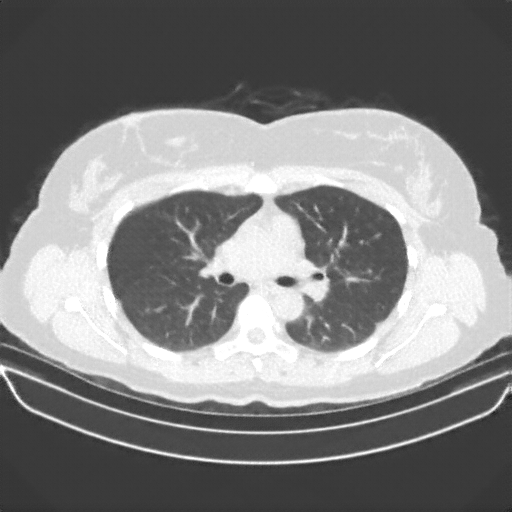

Image Grid

4Γ—3 grid: Rows show different image types (Original NATIVE, Reconstructed NATIVE, Original VENOUS, Generated VENOUS), Columns show windowing techniques (No Window, Lung Window, Mediastinum Window)

Original NATIVE CT scan (input)

Lung window (WL -600, WW 1500 β†’ Low βˆ’1350, High +150)

Original VENOUS CT scan

Generated VENOUS CT scan (A→B translation)